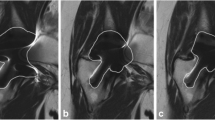

The angle formed by the legs of the inner margins of the os ilium and the acetabular roof in the coronal center slice of the hip, the acetabular roof angle (ARA), was used to measure the distortion (Fig. 2). Measurement of the right and left hip in MR examinations of ten patients without THA showed an ARA > 150° (Table 2). The artifact area was measured by visual outlining of the artifact (defined as the area with signal void and pile-up artifacts, i.e., low and high signal) in the location of the prosthesis and surroundings (Fig. 3). The artifact area was delineated in the central slice through the prosthesis with the largest area as described by Sutter at al. [10]. The examinations were reviewed by two experienced musculoskeletal radiologists, BL with >25 years and GM with 8 years of musculoskeletal radiology experience.

The ARA varied with the different MARS sequences (Fig. 4). The angle was smaller than normal in T1-hiBW and STIR-mRFp in all prostheses and in the VAT in the MoM prostheses. The T1 VAT + SEMAC showed a normal angle in MoM as well as non-MoM prostheses. The statistics of the measured angles are listed in Table 3. Comparing the different prostheses, the ARA was smaller in the MoM compared to the non-MoM prostheses, i.e., showed more distortion in the first type. In both MoM and non-MoM prostheses, the t-test showed significantly less distortion in T1 VAT + SEMAC than T1-hiBW (p < 0.001 and = 0.006, respectively), in T1 VAT + SEMAC than T1 VAT (p < 0.001 and = 0.014) and in T1 VAT than T1-hiBW (p < 0.001) (Fig. 5). Comparing the distortion between MoM and non-MoM prostheses, the Wilcoxon-Mann-Whitney test revealed significantly more distortion in MoM prostheses (Table 4). The ARA could not be measured in STIR-hiBW because of the large artifact size.